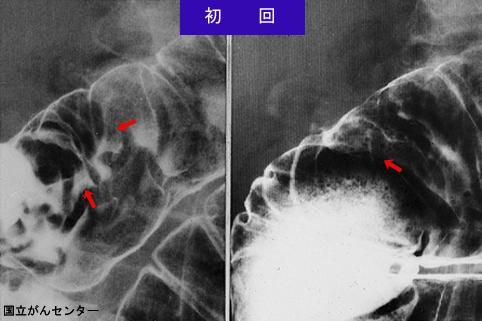

症例提示(所在地,施設名等): 東京都・ 国立がんセンター中央病院と九州がんセンターの共同作成

疾患(病理主体)の分類悪性上皮性腫瘍/腺癌

部位(臓器別)十二指腸/下行脚

検査方法X-P

腫瘍の肉眼分類0型(表在型)/I型(Is)

病変の最大径(ミリ)25〜29

腫瘍の深達度m